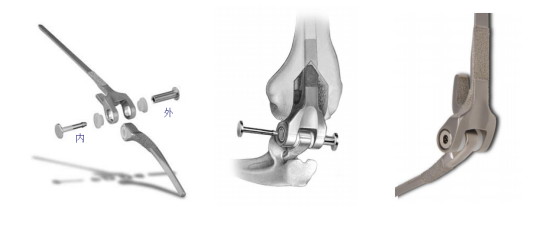

人工肘关节置换手术是指用人工肘关节代替损坏的肘关节。人工肘关节假体一部分固定在上臂的肱骨中,另一部分则固定在前臂的尺骨中,两部分以轴承连接,完成人工肘关节屈曲功能。该手术的目的主要是为了减轻患者疼痛、恢复肘关节功能以满足正常生活的需要。人工肘关节置换在我国经过了好几代的改进,Coonrad/Morrey的假体已有30余年的历史,经历了多次的迭代和发展,假体设计结合肘关节的生物力学不断改进,提高患者满意率。陈志伟还说:“运用Coonrad/Morrey最新的假体实施手术,肘关节截骨量少,可尽量保留患者的骨质,对原本的骨质破坏少,假体寿命更长、功能更好,患者康复更快,同时也为远期的肘关节翻修保留了机会。”

肘关节假体示意图